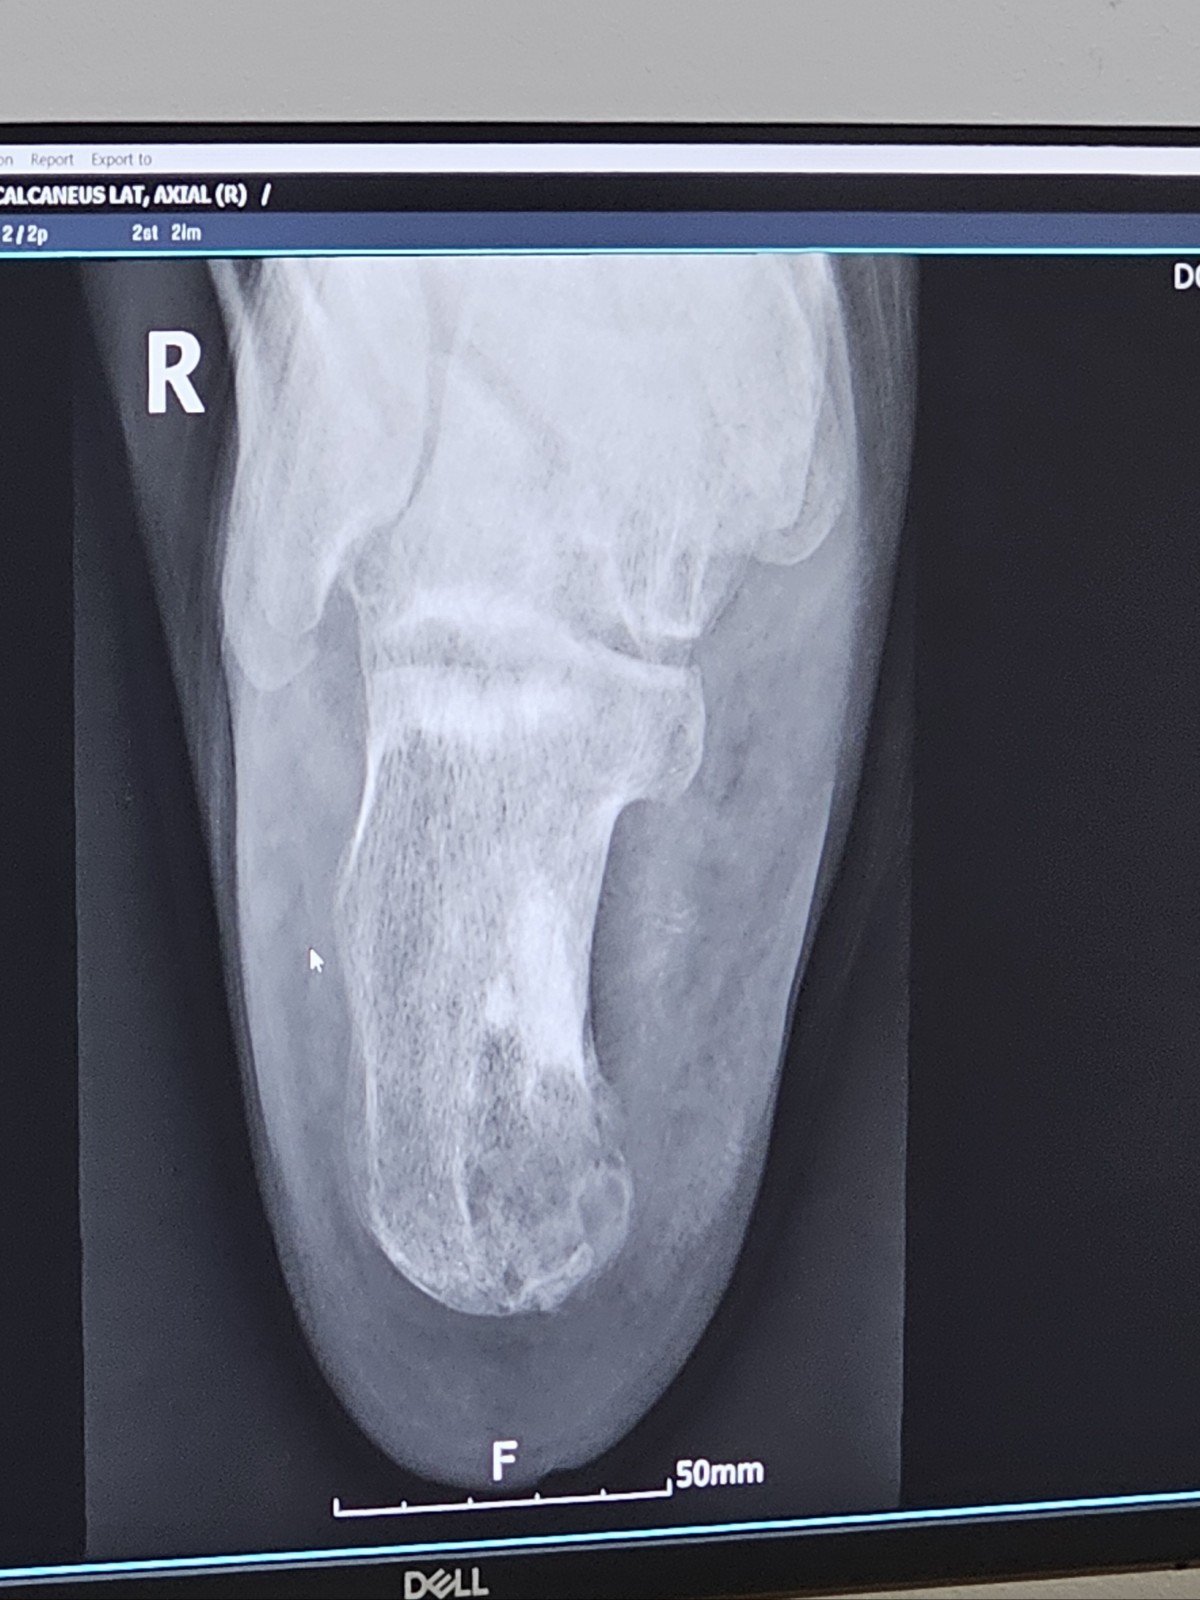

종골 양성종양 제거 후 골수염진단 및 뼈이식 대기중인 환자입니다.

25년7월 종골 양성종양 제거 후 칼슘시멘트 삽입

25년8월 염증 증상으로 동일병원에서 11월까지 항생제치료하였으나 호전없어

25년11월중순 대학병원 수술 - 불유합된 시멘트 일부 제거하였으나 잔존시멘트 제거불가, 제거시 종골 무너진다고 판단 / 그 이후 4차례 변연절제술, 6주간 IV항생제치료 및 뼈이식 대기중이나 잔존시멘트에 의한 분비물 지속 발생(감염내과 추정) / 남은 종골이 50% 정도뿐인데다가 잔존시멘트가 깊숙히있어 제거불가한데 분비물은 계속나오고 절단, 종골포기 등 암담한 진단에 하루하루가 지옥같습니다.

현재는 골수염 치료가 우선이라하여 뒤꿈치쪽 상처 열어놓은상태로 패킹드레싱 및 경구항생제를 자택에서 치료중입니다.

첨부한 엑스레이사진은 11월중순 수술하고 나와서 항생제 시멘트를 넣어둔상태에서 엑스레이사진입니다. 현재는 항생제 제거 후 봉합없이 오픈상태입니다.

종골에 남은 시멘트를 제거 후 뼈이식은 할수없는것인지, 잔존시멘트를 제거못하면 이상황이 계속 지속될것같은데 항생제도 경구, IV합쳐서 작년8월부터 복용치료중입니다.

골수염이라는게 시간이 필요하지만 저는 잔존시멘트가 감염의 원인이 남은 상태로 치료하고있는게 더더욱 암담하고 결국 종골을 포기해야하는 상황인지..